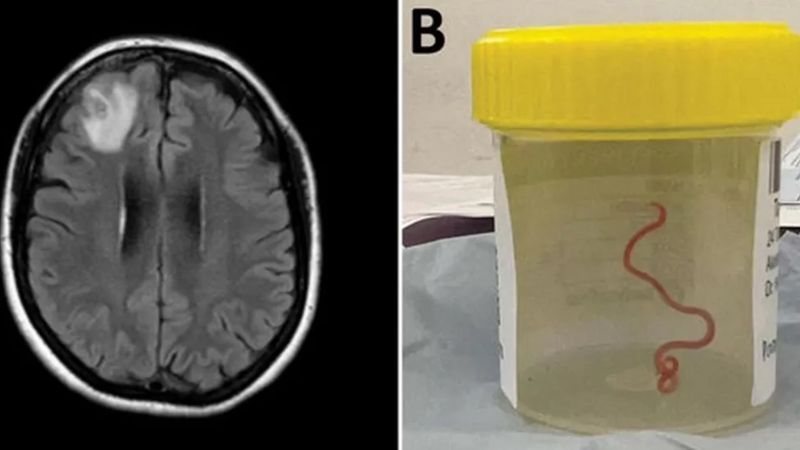

Ku nshuro ya mbere ku isi, abahanga muri siyanse baravuga ko inzoka ya 8cm bayisanze ari nzima iri mu bwonko bw’umugore wo muri Australia.

Iyi nzoka bayivanye mu gice cy’imbere cy’ubwonko bw’uyu mugore cyari gifite ikibazo, mu kubaga kwabereye i Canberra umwaka ushize.

Iyo nzoka y’umutuku yari imaze amezi abiri mu bwonko bwe.

Sanjaya Senanayake, umuganga w’indwara zandura wo mu bitaro bya Canberra, yagize ati: “Buri wese wari muri uko kubaga yaratunguwe birenze ubwo ubaga yakoreshaga agafashi akavanamo ikidasanzwe kinyagambura, inzoka nzima itukura ya 8cm.

Uyu murwayi yashyizwe mu bitaro mu mpera za Mutarama(1) 2021. Nyuma ikizami cya ‘scan’ cyerekanye “agace kadasanzwe k’umubiri mu gice cy’imbere cy’ubwonko”. Impamvu y’uburwayi bwe yamenyekanye neza bamubaze muri Kamena(6) 2022.